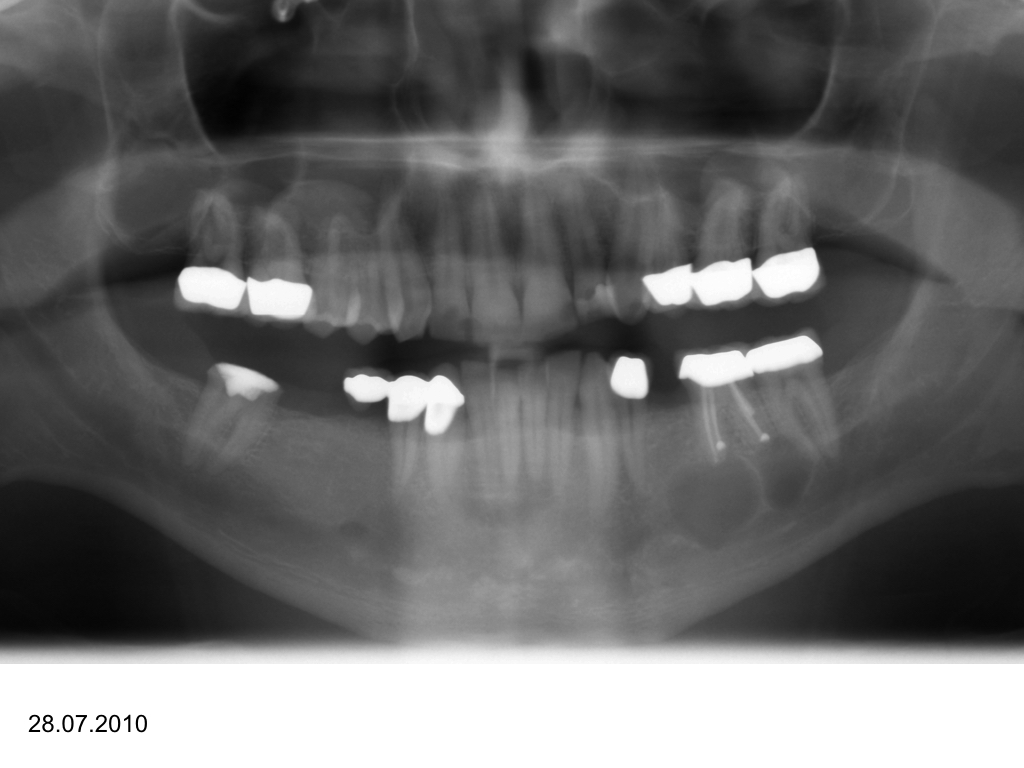

WS_Zy UK.004

Eine Fallvorstellung (2)